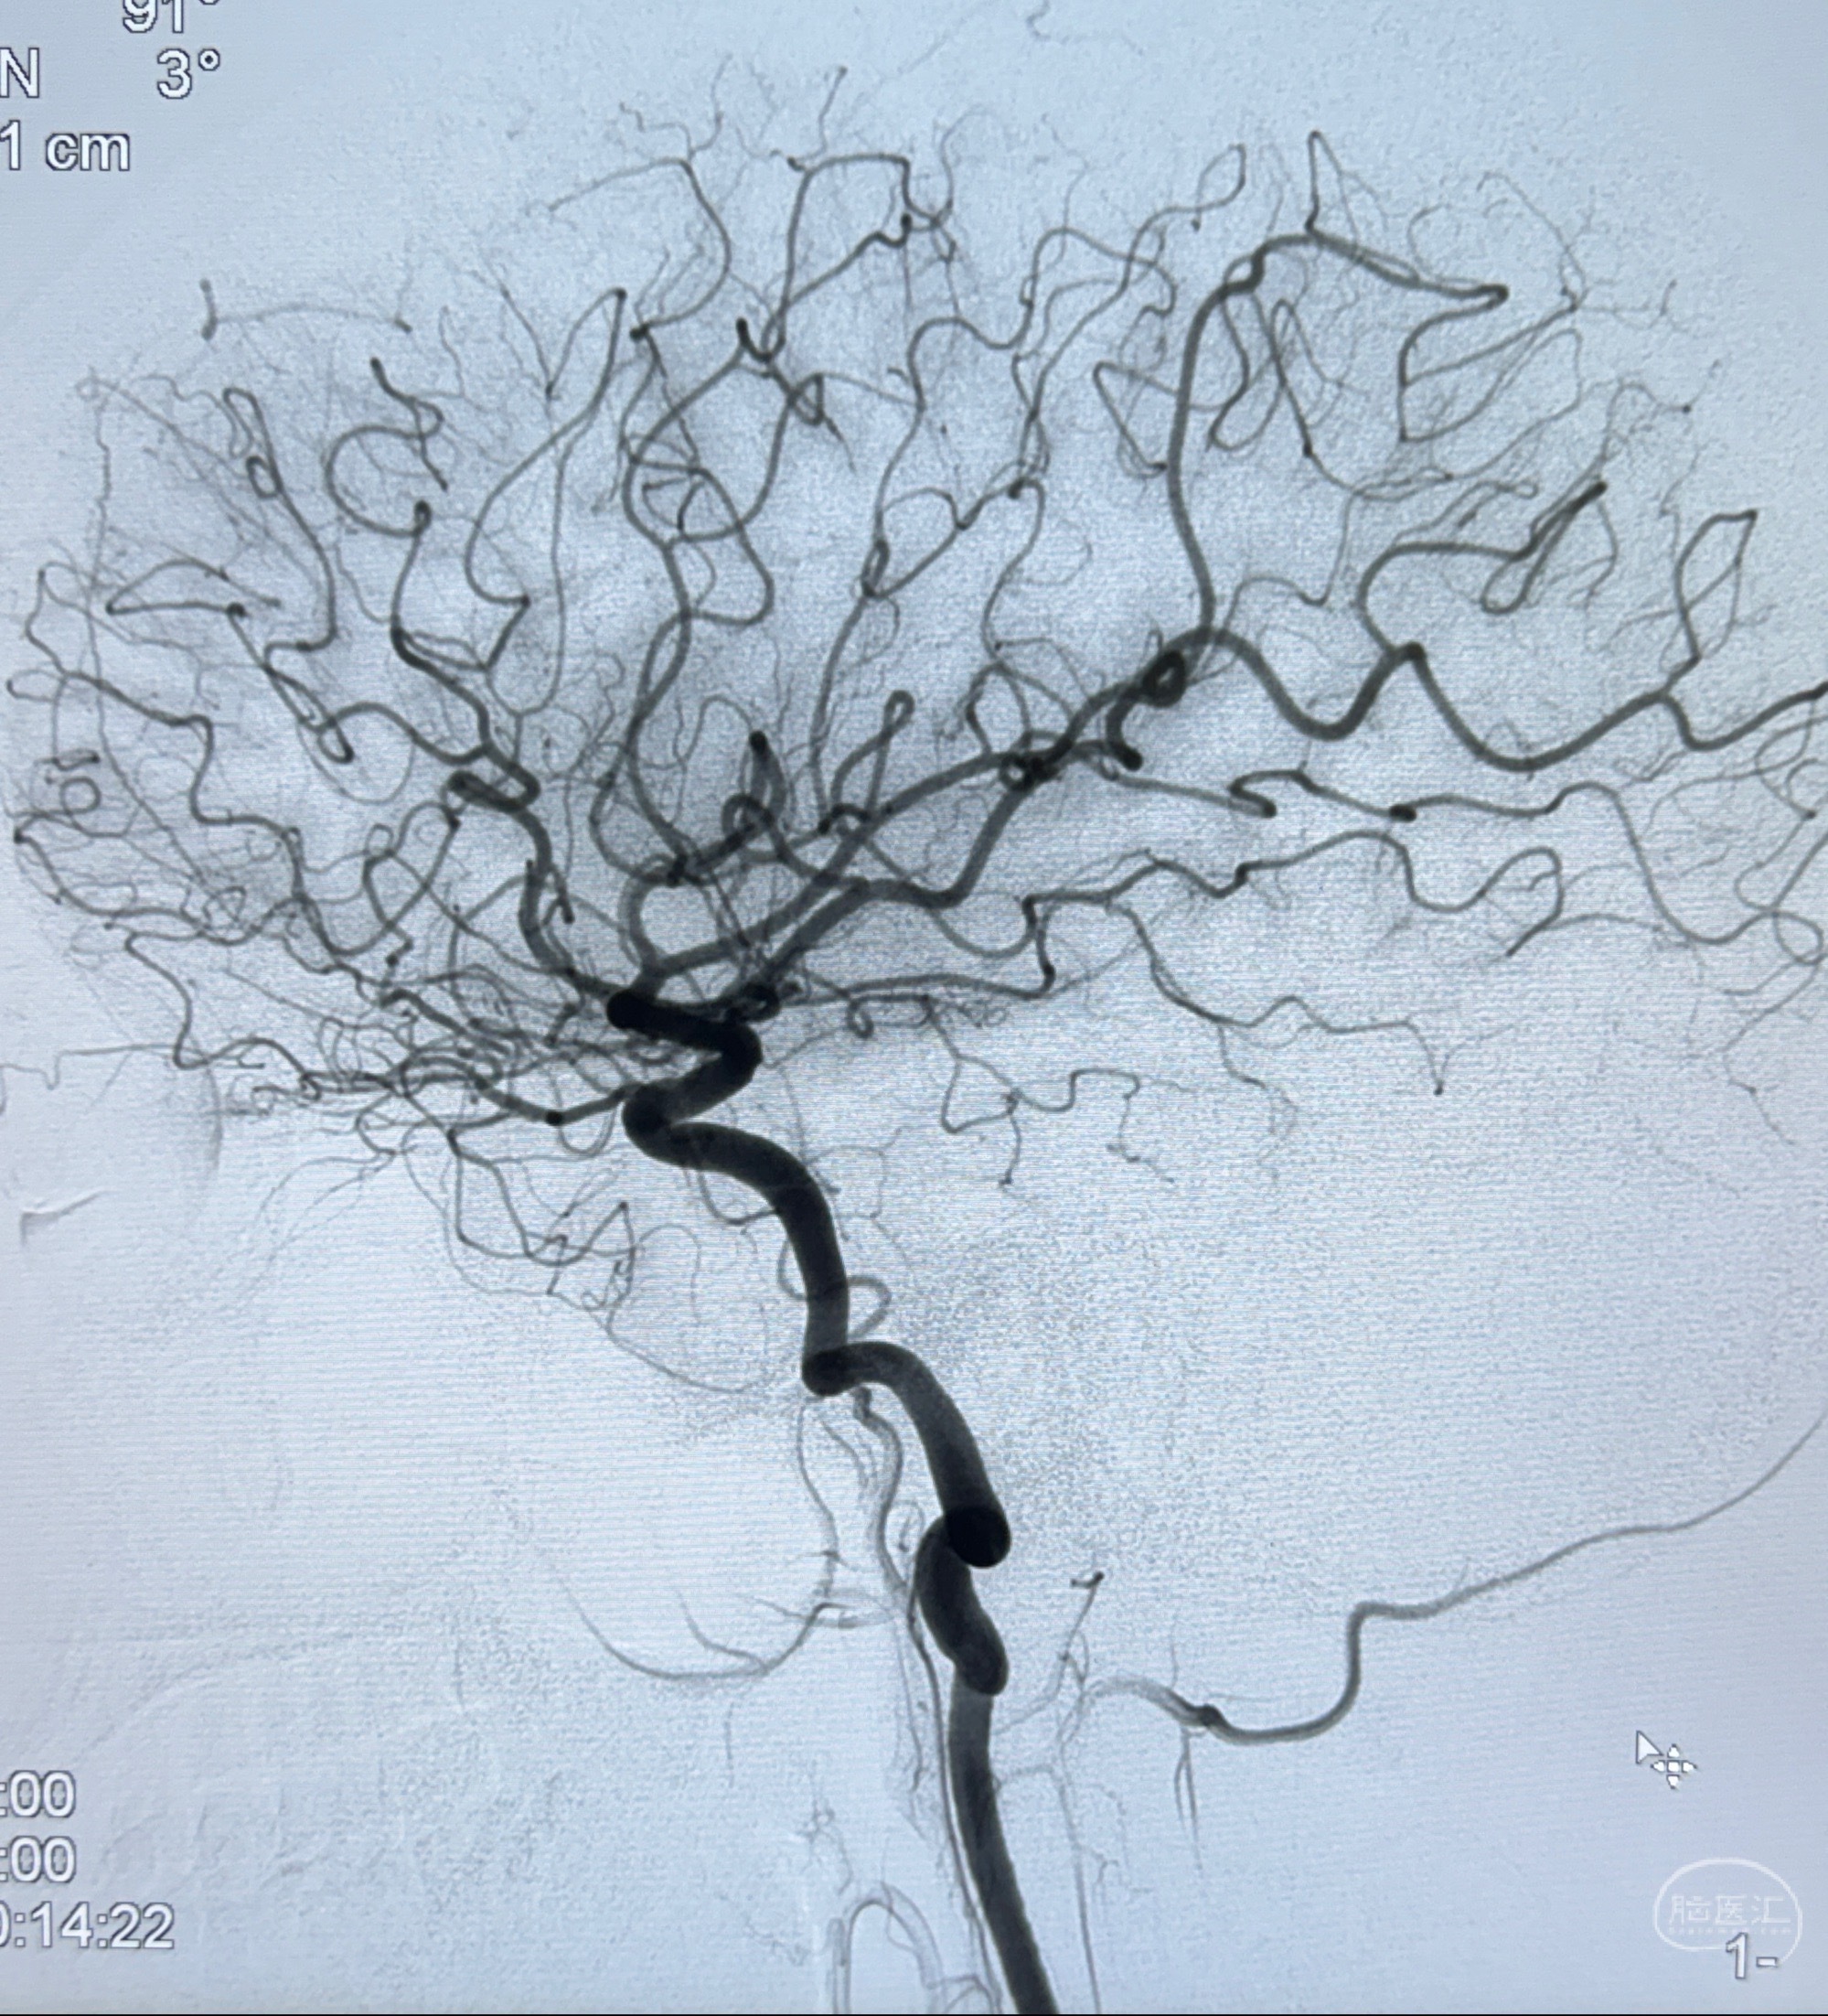

现病史:患者诉近4年来时有头痛发作,服用都梁软胶囊、氟桂利嗪对症治疗一月后症状改善,后头痛较少发作。近3月来患者头痛发作频率明显增加,约一月一次,为右侧偏头痛,胀痛,伴恶心呕吐,呕吐后症状可略减轻;遂于2023-11-01至蓝十字脑科医院就诊,查头颅MRI+DWI+MRA提示:左侧枕叶皮层下小斑片缺血或变性灶,右侧大脑前动脉A1段毛糙,显影淡、纤细,建议完善CTA;并于2023-11-03查头颅CTA提示:左侧颈内动脉C6段微小动脉瘤可能(约2mm),右侧大脑前动脉A1段纤细(对侧优势),左侧大脑中动脉提前分叉。现患者无明显不适,为求进一步诊疗颅内血管病变至我科就诊,收治入院。

2023-11-03 蓝十字脑科医院 头颅CTA:左侧颈内动脉C6段微小动脉瘤可能(约2mm),右侧大脑前动脉A1段纤细(对侧优势),左侧大脑中动脉提前分叉。

1.左侧颈内动脉瘤